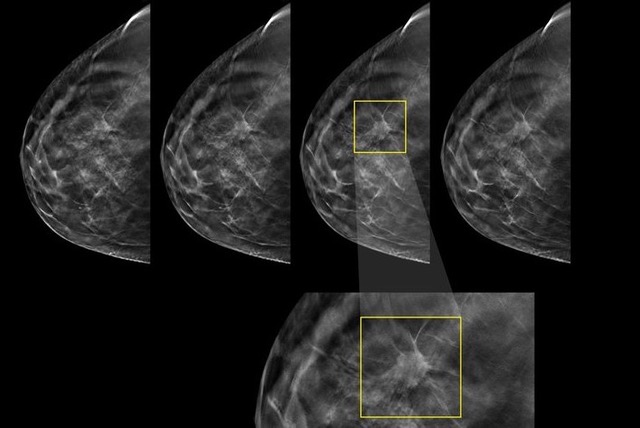

HD-Tomosynthese

Die Tomosynthese (3D) erzeugt im Gegensatz zur herkömmlichen digitalen Mammographie (2D) eine Serie von Schichtaufnahmen, die eine „dreidimensionale“ Sicht der Brust ermöglicht. Dadurch sollen Überlagerungen von Gewebestrukturen ausgeblendet und das Brustdrüsengewebe besser beurteilbar werden. Röntgendichte oder unregelmäßige Drüsenkörper können die Erkennung von Tumoren in der Mammographie erschweren – hier bietet die HD Tomosynthese einen deutlichen Vorteil!